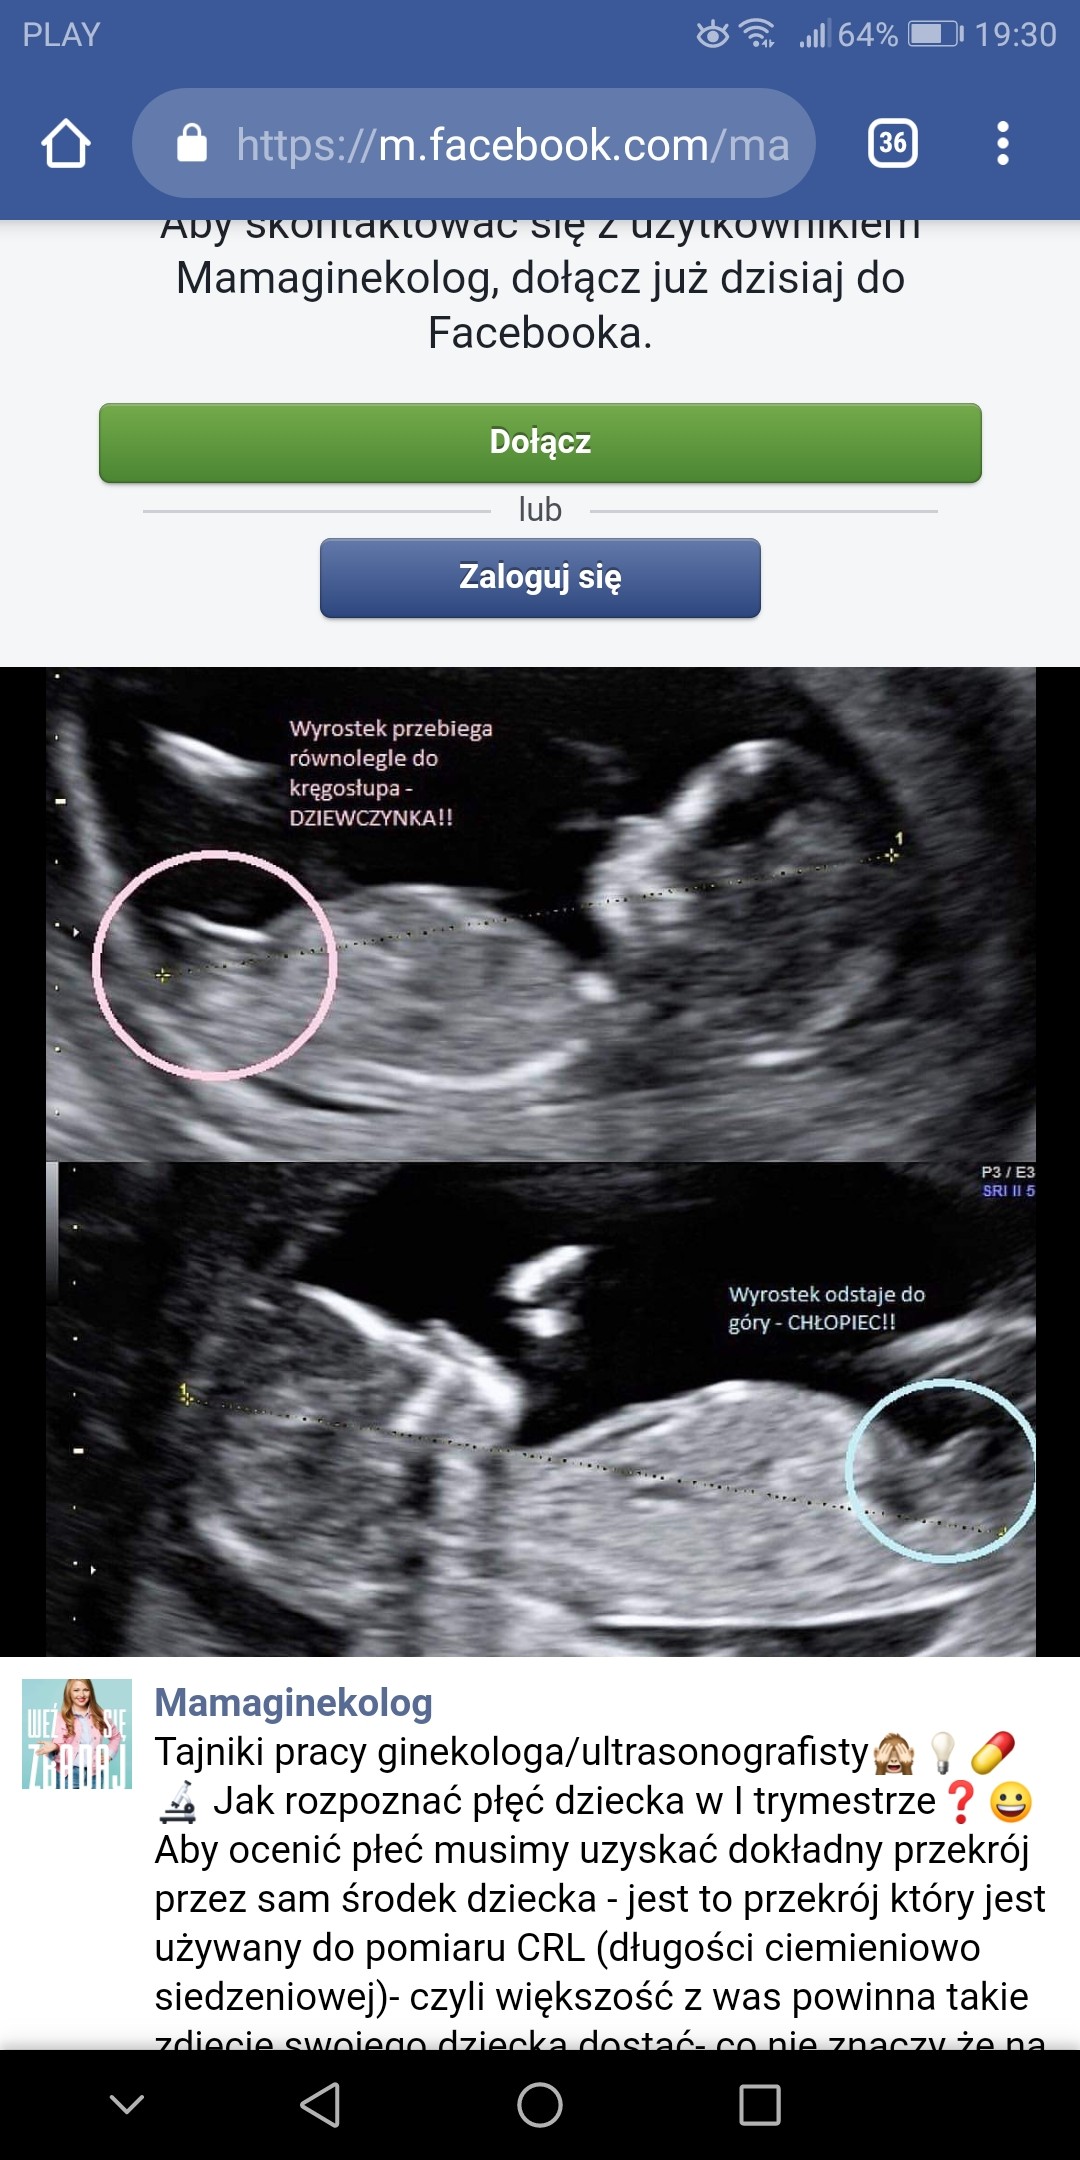

Ja w sumie na USG w 9 tygodniu, które miałam robione w szpitalu, przez jakieś stazystki pod okiem lekarza też usłyszałam, że to chyba chłopak, bo coś tam widzi :p a potem wyczytałam, że w 9 tygodniu to narządy płciowe dziewczynek i chłopców wyglądają bardzo podobnie i to za wczesnie żeby oceniać. Więc uważam, że jeśli płeć ustalona w 9tc się sprawdzi, to jest to czysty przypadek, a szanse są dokładnie 50 na 50 ;)

Metoda wspominana wyzej

Ja w sumie na USG w 9 tygodniu, które miałam robione w szpitalu, przez jakieś stazystki pod okiem lekarza też usłyszałam, że to chyba chłopak, bo coś tam widzi [emoji14] a potem wyczytałam, że w 9 tygodniu to narządy płciowe dziewczynek i chłopców wyglądają bardzo podobnie i to za wczesnie żeby oceniać. Więc uważam, że jeśli płeć ustalona w 9tc się sprawdzi, to jest to czysty przypadek, a szanse są dokładnie 50 na 50 ;)

Screenshot_20190820-113720_Chrome.jpeg

Byłam w szpitalu wtedy i młoda lekarka powiedziała mi, że widzi chłopca, bo taka mała kreseczka była skierowana ku górze, a jak jest równolegle z kręgosłupem, to dziewczynka. Kazała oczywiście tak do końca nie sugerować się tym, bo było wcześnie, ale powtórzyła, że widzi chłopca. I na prenatalnych z grubej rury do mnie, że widać jak coś, że to chłopak. Dlatego mam nadzieję, że penisa ma normalnych rozmiarów :D

Gdzieś ze stronki. Tu jest większe dziecko, ale mi w 9+3 powiedziała. Też się zdziwiłam, że tak szybko mogła ocenić. Szpital ma lepsze usg